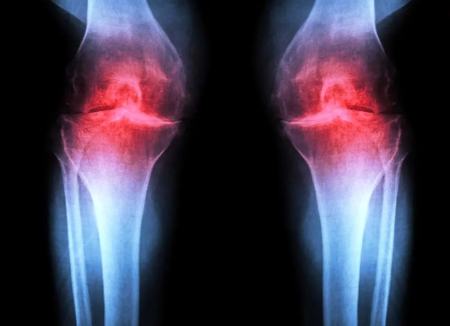

آرتروز زمانی رخ می‌دهد که مفصل بر اثر پیری، آسیب یا چاقی تحت فشار قرار گیرد. کندروسیت‌ها شروع به آزادسازی مولکول‌های پیش‌التهابی و تجزیه‌ی کلاژن (پروتئین ساختاری اصلی غضروف) می‌کنند. با از دست رفتن کلاژن، غضروف نازک و نرم می‌شود و التهاب همراه، تورم و درد مفصل را (که از ویژگی‌های بارز بیماری است) ایجاد می‌کند. در شرایط عادی، غضروف مفصلی به‌ندرت بازسازی می‌شود. اگرچه برخی جمعیت‌های فرضی از سلول‌های بنیادی یا پیش‌سازِ قادر به تولید غضروف در استخوان شناسایی شده‌اند، تلاش‌ها برای یافتن جمعیت‌های مشابه در غضروف مفصلی موفقیت‌آمیز نبوده است.

سپس آن‌ها با تزریق یک داروی مولکول کوچکِ مهارکننده‌ی 15-PGDH به حیوانات پیر (ابتدا به داخل شکم با اثر سیستمیک و سپس مستقیما به مفصل) آزمایش کردند. در هر دو حالت، غضروف زانو که در حیوانات مسن نسبت به موش‌های جوان به‌طور محسوسی نازک‌تر و کم‌کارتر بود، در سراسر سطح مفصل ضخیم‌تر شد. آزمایش‌های تکمیلی تأیید کرد که کندروسیت‌های مفصل در حال تولید غضروف هیالین (مفصلی) هستند، نه فیبروغضروفِ کم‌کارتر.